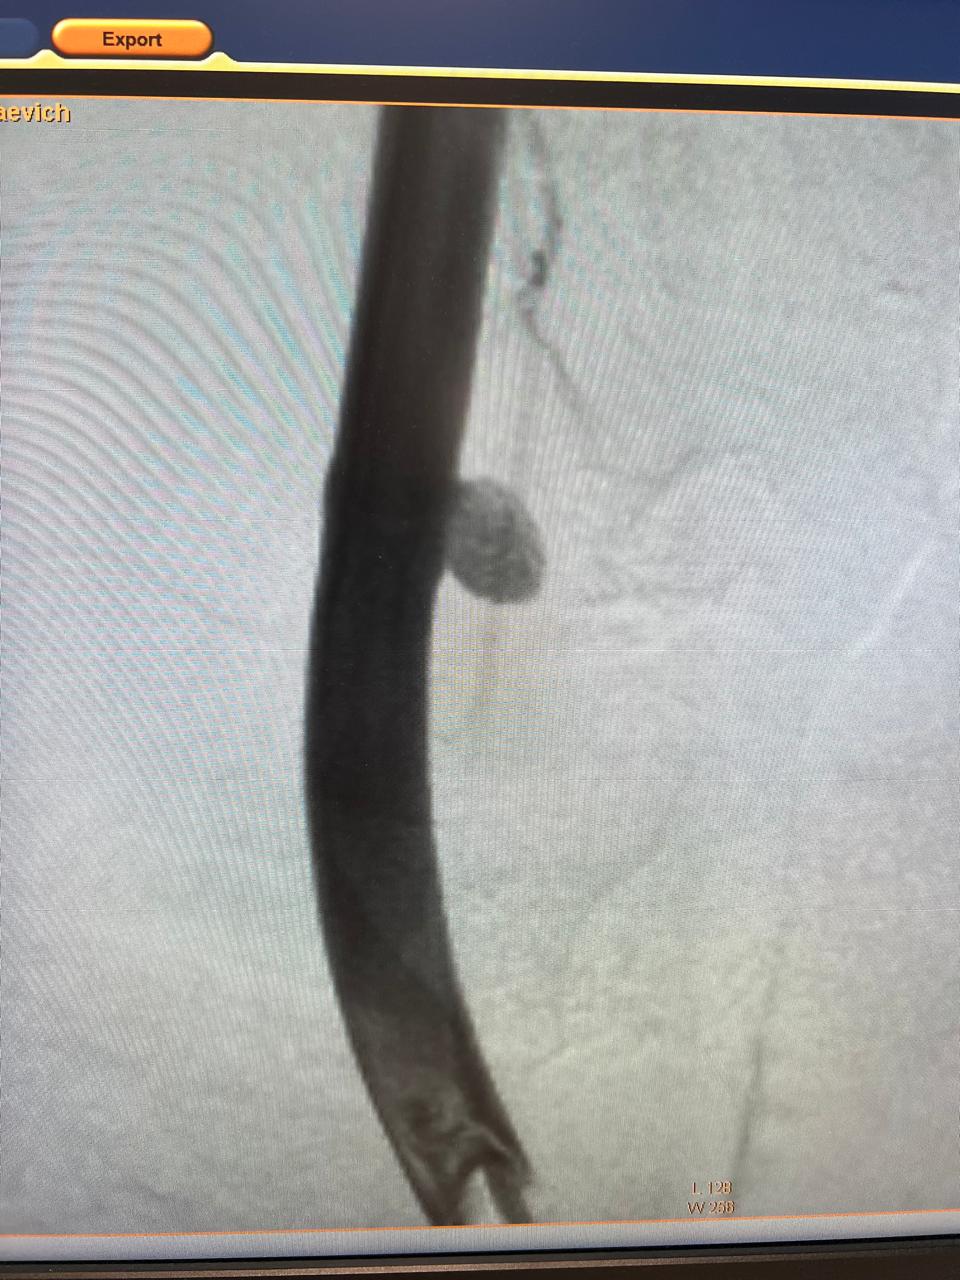

В Курской областной больнице медики провели сложную операцию пациенту, у которого после ранения развилась аневризма сонной артерии. Вместо открытой хирургии хирурги применили малотравматичную технику, сохранив больному жизнь.

Тридцатидвухлетний мужчина получил тяжёлое повреждение яремной вены и сонной артерии вследствие удара беспилотника. После лечения в клиниках Курска и московского Института Склифосовского пострадавшего отправили домой. Но осложнения травмы вскоре проявились вновь: ультразвуковое исследование выявило аневризму сонной артерии — опасное растяжение её участка с утончённой стенкой.

Под местным обезболиванием специалисты Валерий Казанов и Алексей Подтуркин проделали маленький надрез в бедренной артерии ноги. Используя точное рентгенологическое оборудование нового ангиографического комплекса, врачи ввели миниатюрные инструменты по сосудам до поражённого участка шеи. Затем в артерию установили стент-графт — надёжную трубку из полиэстера с металлической опорой. Она усилила слабую стенку сосуда, защищая его от возможного разрыва. Операция длилась примерно час.